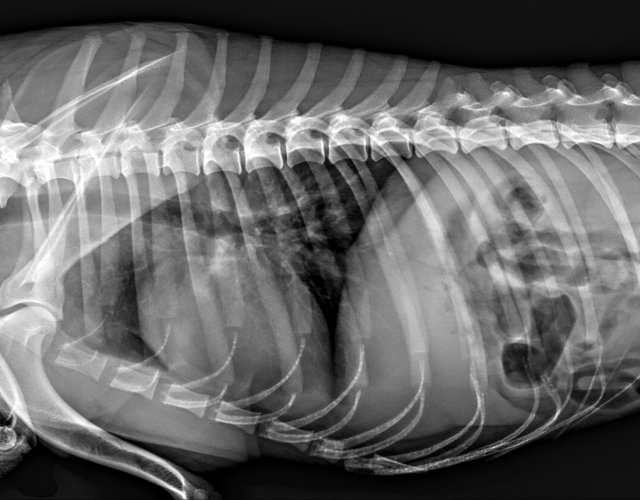

Caine accidentat

O doamna a gasit un caine lovit de masina si l-a tras pe marginea drumului pentru a suna peste tot in cautare de ajutor. Am raspuns pozitiv si am facut totul pentru el. Din pacate nu a putut fi salvat, decedand a doua zi dupa interventia chirurgicala. Foarte probabil din cauza unei embolii pulmonare. Le multumim celor care au donat. Medicul a anulat factura iar banii vor ajuta desigur alte animale de care ne ocupam zilnic.